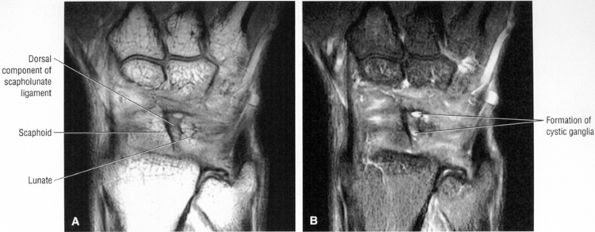

![]() |

FIGURE 10.90 ● Scapholunate ligament tear with DISI. (A) Traumatic avulsion of the lunate aspect of the scapholunate ligament on a fast STIR coronal image. The scapholunate interval is widened with direct extension of fluid filling the tear site (large straight arrow). Ligament fibers are still attached to the radial aspect of the lunate (small straight arrow). Morphology is amorphous at the avulsed scaphoid remnant (curved arrow). (B) The capitolunate angle (arrow) is increased to 46°, and there is associated dorsal tilting of the lunate. (C) The scaphoid tilts palmarly with an increased scapholunate angle (arrow) of 142°.